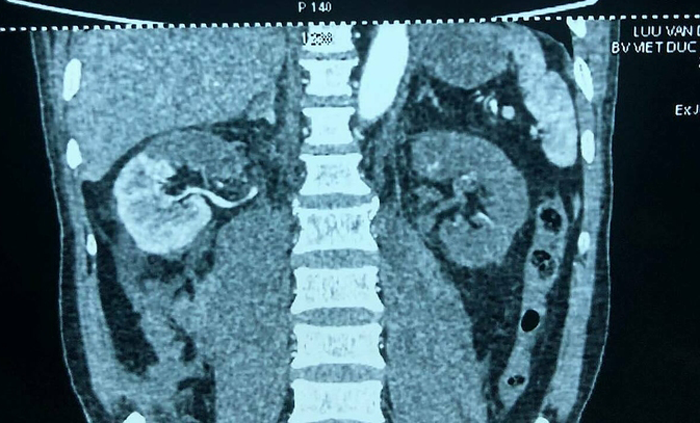

Phim X-quang trước mổ cho thấy thận phải mất 1/2 chức năng, thận trái mất hoàn toàn. (Ảnh: BSCC)